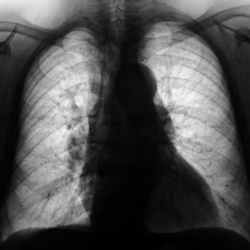

Пациент из областной онкологической "конторы" направлен на рентгенографию ОГК (по месту жительства) с диагнозом "гамартома" - "шутка" № 1.Что скажут уважаемые коллеги?

14.06.2012 - 20:30